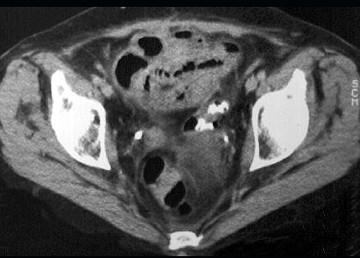

问题 女,54岁,直肠癌放疗后一月,阵发性腹痛腹胀,呕吐应,CT表现如图,应诊断为 ( )

选项 A.小肠淋巴瘤 B.小肠结核 C.小肠Crohn病 D.放射性小肠炎 E.肠易激综合征

答案 D